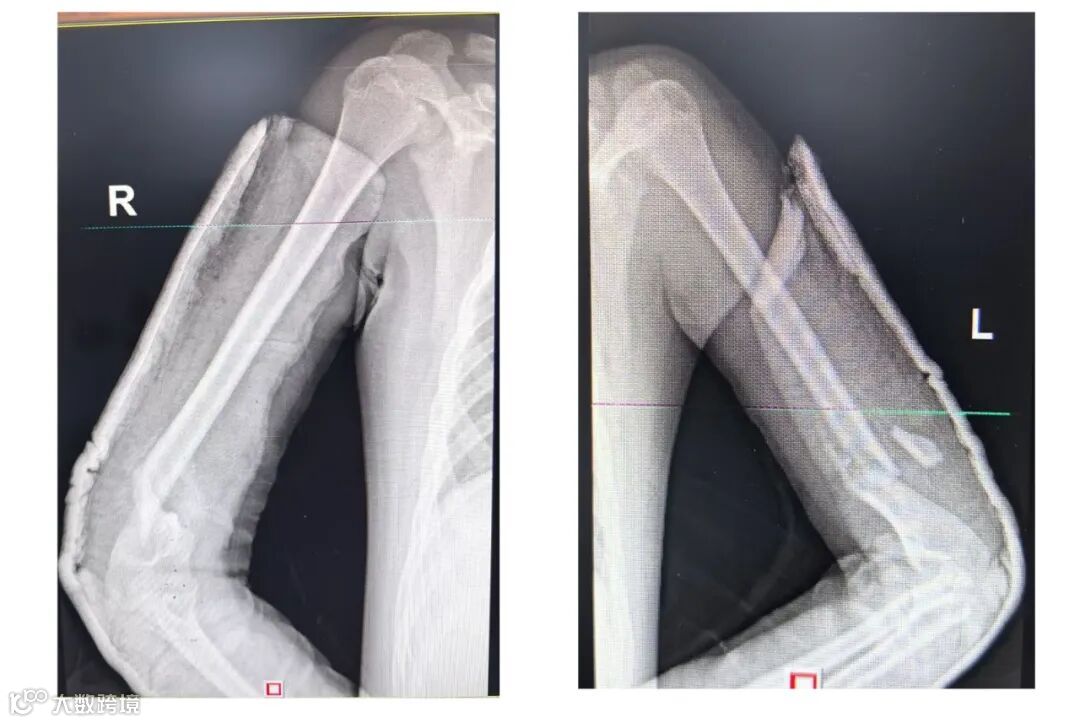

术后,患儿又接连面临脓毒性休克、渗漏综合征、双侧气胸、肺不张等严峻挑战。面对复杂病情,儿科重症团队采取综合治疗,应用床旁重症超声技术,制定精准的液体复苏管理方案,经神经外科、关节脊柱骨科、口腔科等多个科室协助治疗,历经12天全力救治,患儿病情平稳,成功撤离呼吸机。

患儿现能自主进食,与他人能良好沟通交流,恢复良好,现患儿经骨科手术后在骨科进行骨折康复。患儿从一个濒死的危重患者,经过多科联合抢救,克服重重困难,恢复良好,创造了生命的奇迹。